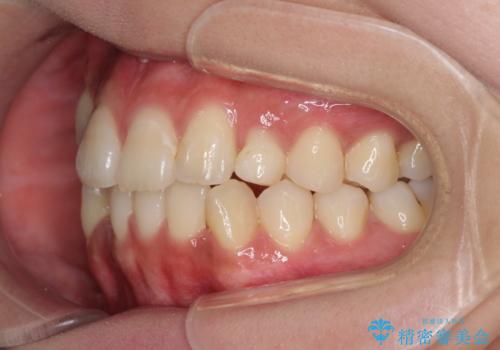

- 前歯のデコボコと残っている乳歯の部分へのインプラント治療を希望して来院された患者様です。

当初は目立たない上下裏側矯正を希望されていましたが、歯並びの悪さによる磨き残しが多く、歯肉炎が認められたため、より清潔な環境で治療を進められるインビザラインを選択することとしました。

前歯のデコボコが強かったため、上の奥歯を後方に動かす量が多くなり、結果として2年以上の治療期間を擁することとなりました。

歯並びが整ったことで治療前に認められた歯肉炎は全くなくなり、患者様には大変満足していただきました。